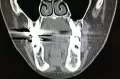

Мне сделали компьютерную томограмму, и на 4 зубах обнаружили кисты от 2 до 6.5 миллиметров. Как лучше начать лечение, и каким способом?

• Если это действительно кисты, то возможно проведение резекции корней зубов, либо их удаление. Конечно, лучше попытаться сохранить зубы и провести качественное лечение корневых каналов и резекцию